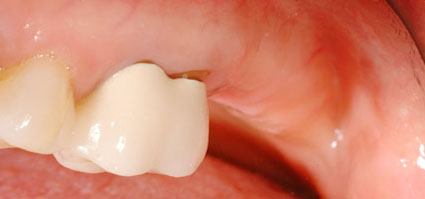

Hình: cấy ghép Implant trước và sau khi phẫu thuật. Vì khi mất răng, mạch máu và thần kinh tại nơi đó sẽ bị tiêu đi, nên việc cấy ghép Implant sẽ ít “nhạy cảm” và cũng ít chảy máu hơn so với khi nhổ răng.

Trong trường hợp bạn nhổ răng kết hợp với cấy ghép Implant trong 1 lần phẫu thuật, trụ Implant sẽ đóng vai trò như một phần của cơ thể bạn trong ổ răng sau khi nhổ, nên thời gian lành thương sẽ nhanh hơn và cũng dễ dàng hơn, vì bình thường thì cơ thể phải tái tạo lại toàn bộ xương bị mất đi khi nhổ răng nên sẽ lâu lành thương hơn.